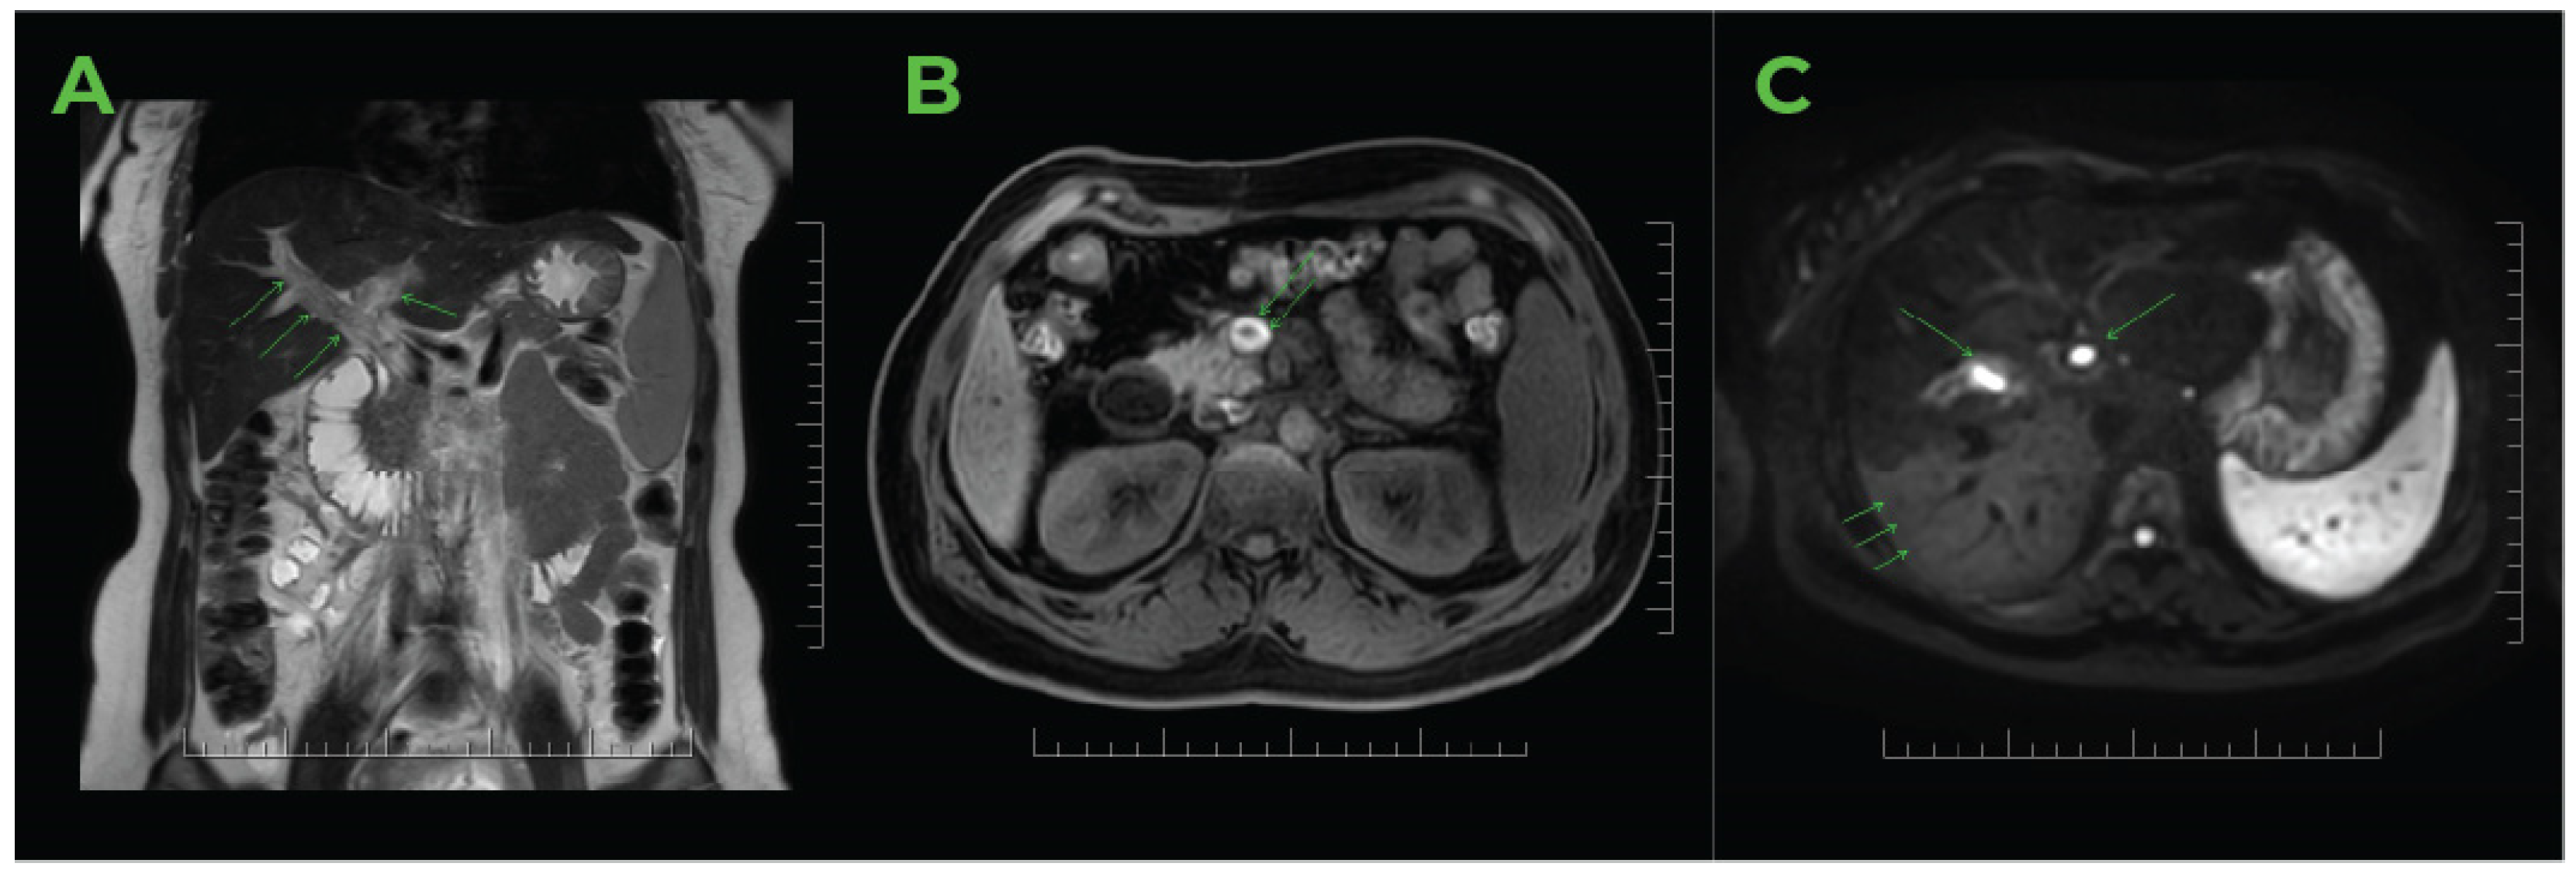

2.2. Imaging Methods